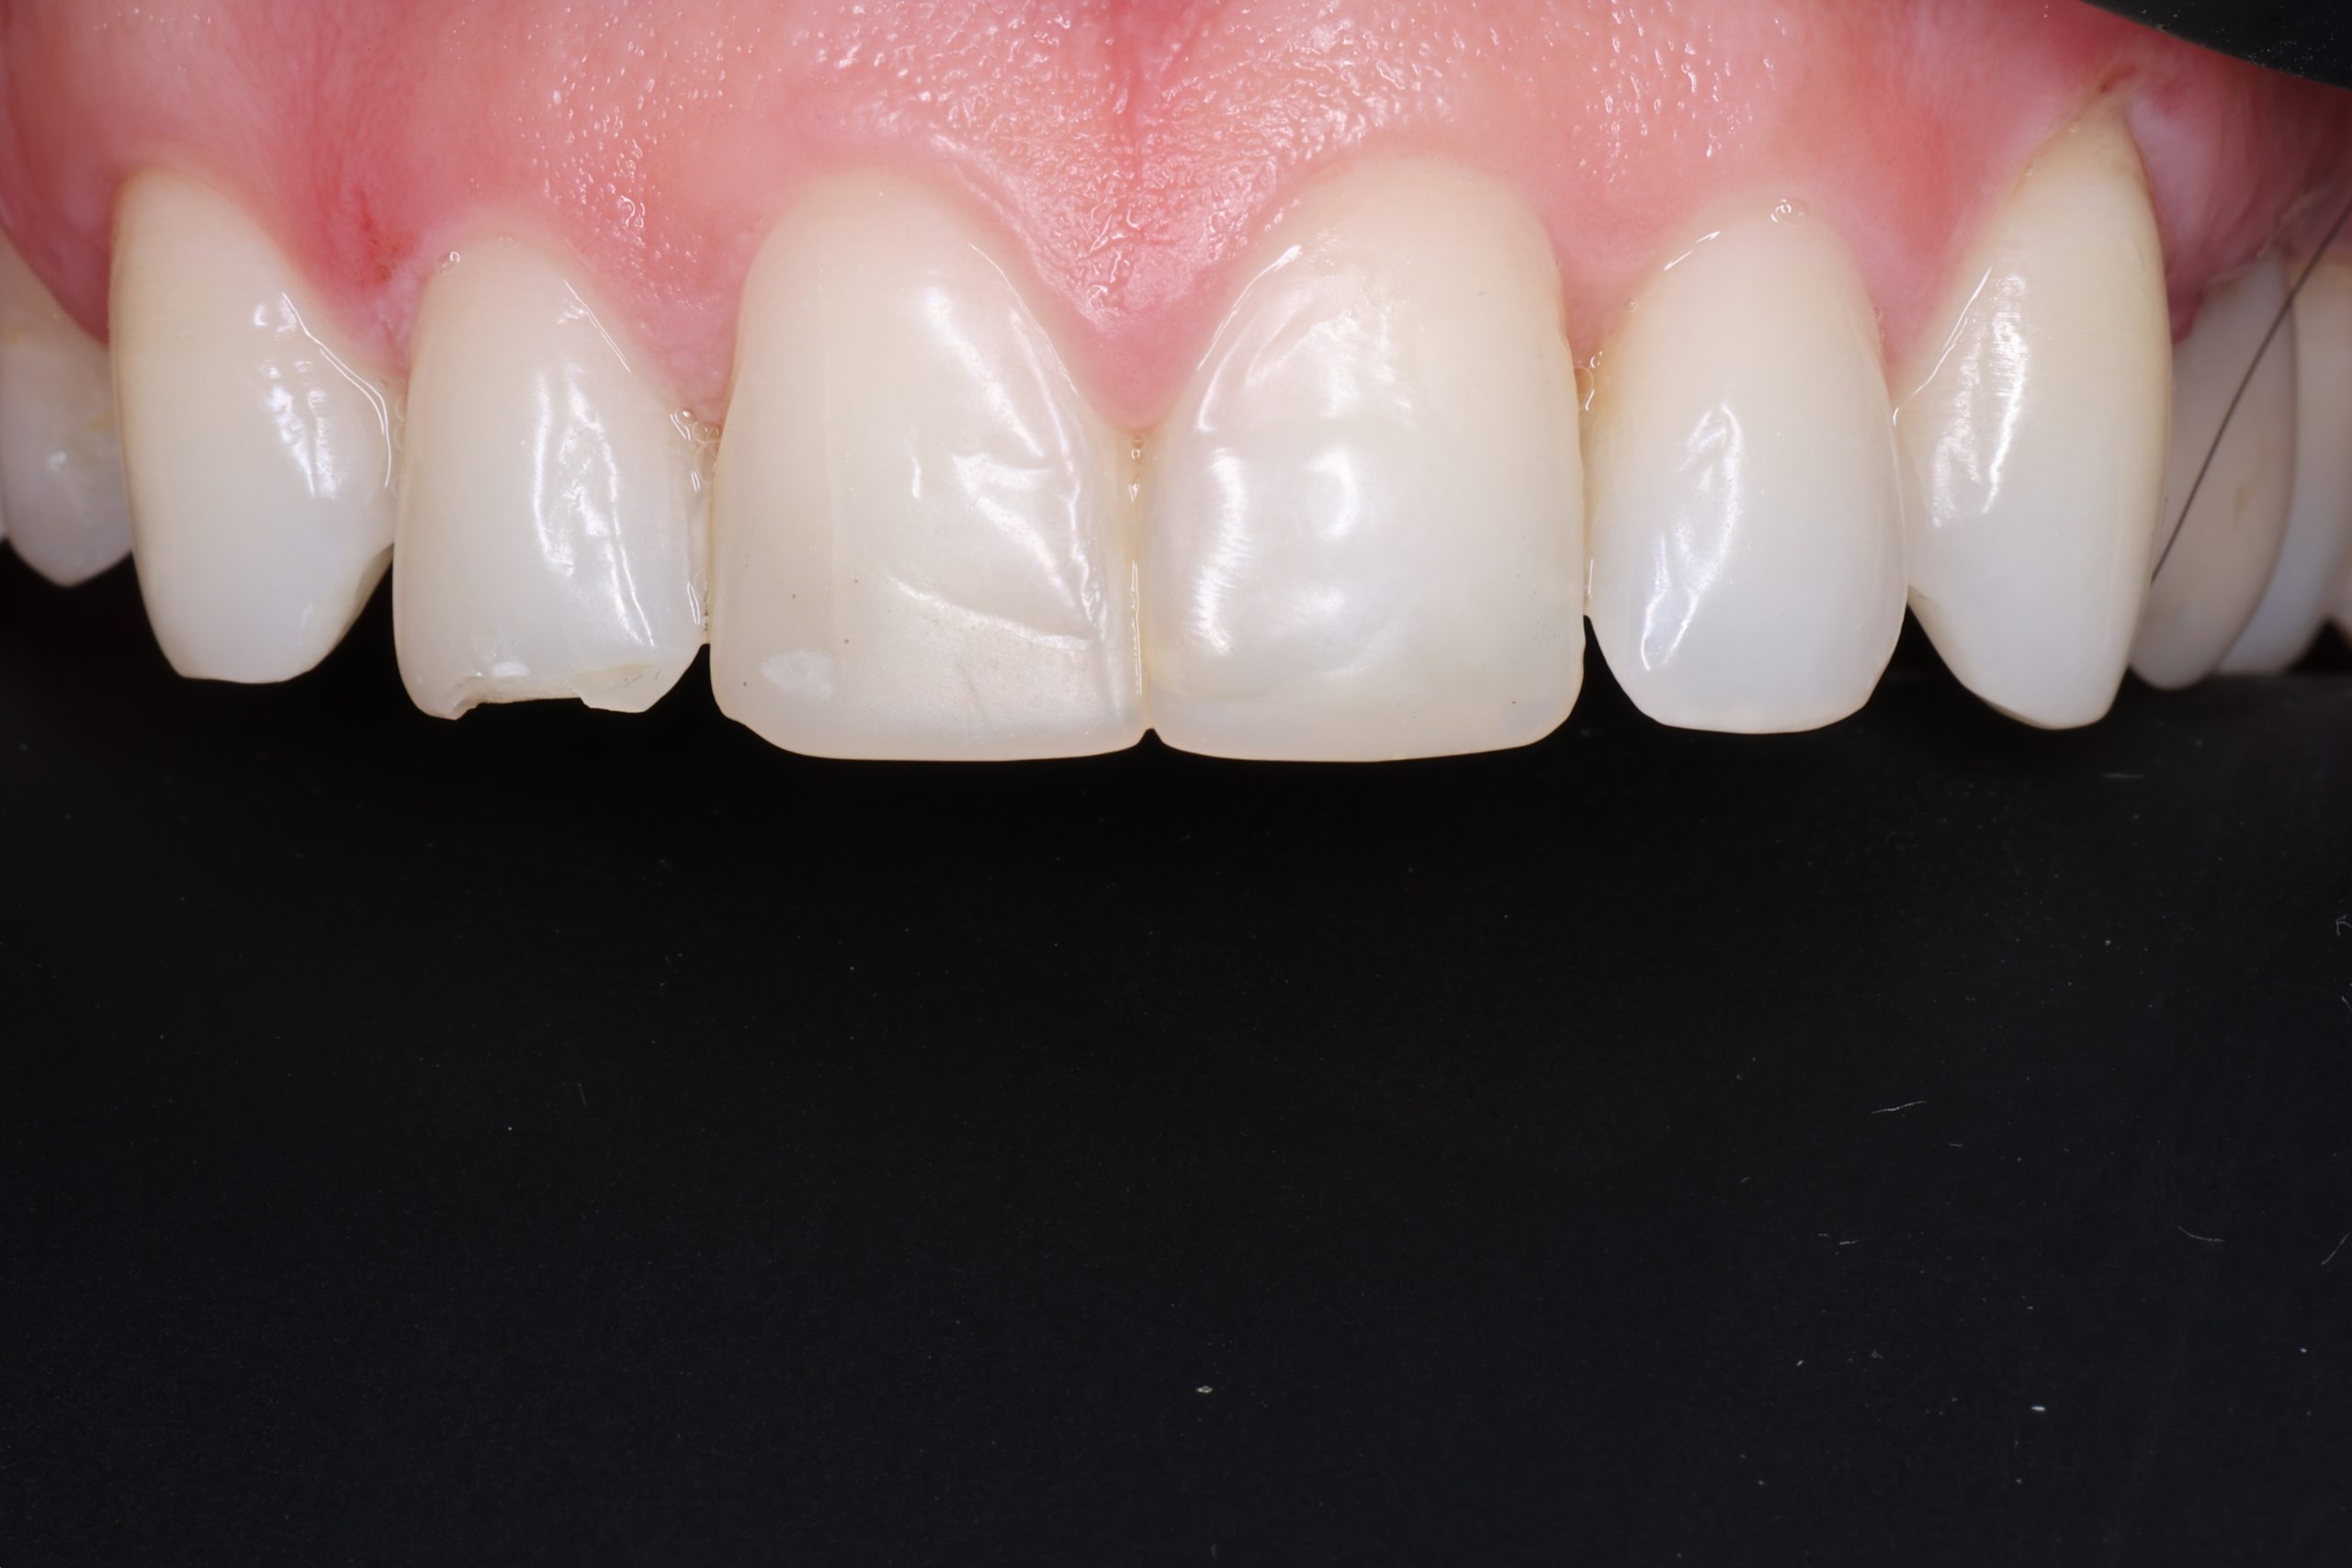

The tooth-coloured resin is applied in thin layers and shaped carefully to match natural anatomy. For front-tooth work, we may combine several shades for a lifelike result.

5. Final Polishing and Bite Adjustment

We contour and polish the surface to a high gloss and ensure your bite feels natural in all positions.

Aesthetic and Natural-Looking

The material matches your enamel, blending into the smile with virtually invisible transitions.